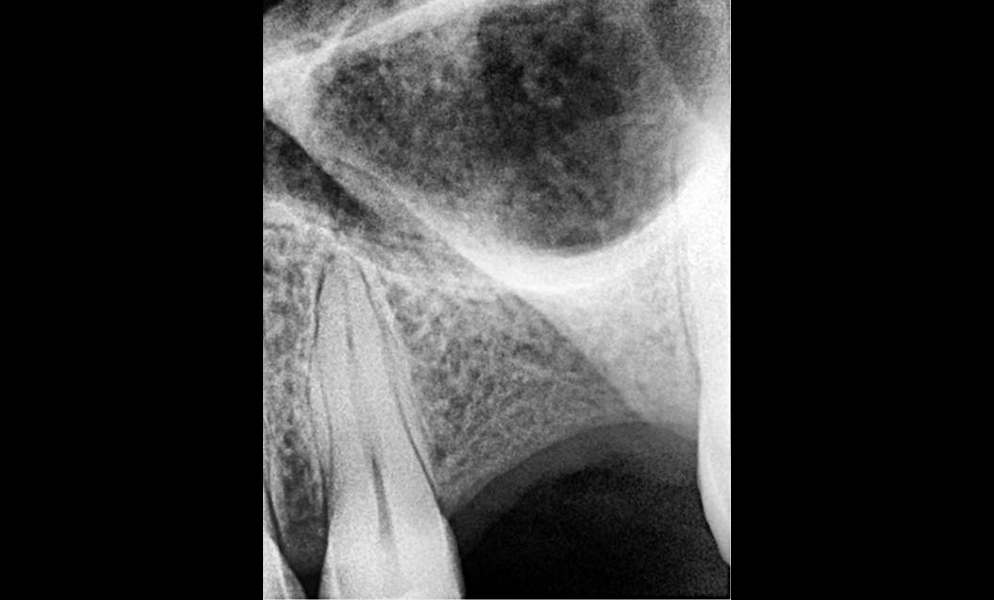

| Before | After |

![]() |

| Single posterior tooth missing space restored with a 5x5 mm short dental implant (Bicon, USA) to avoid sinus lift and bone graft procedures | |